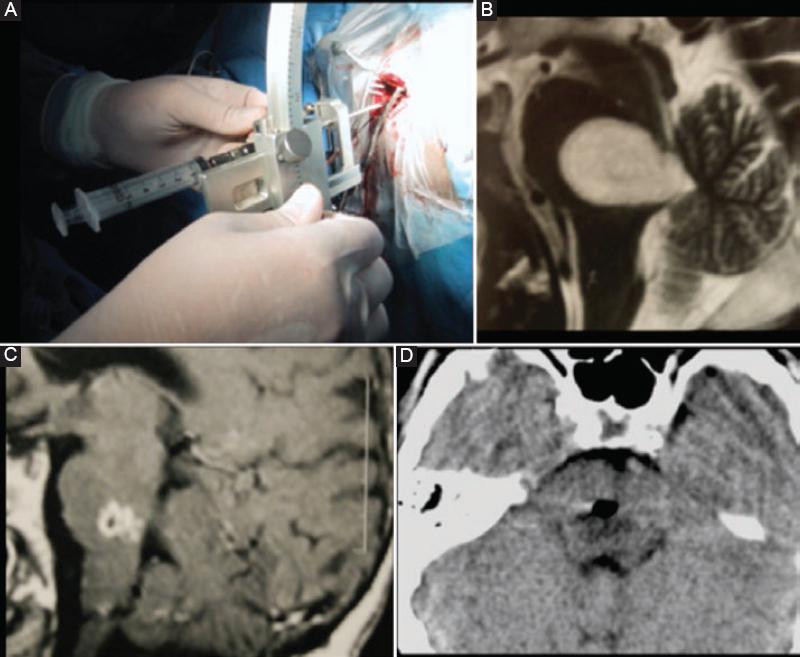

En todos los casos el paciente salió de la sala de operaciones directo a un estudio de tomografía simple de cráneo y a la sala de recuperación (Figs. 2 y 3).

Figura 2 Se muestra uno de los casos en el cual se drenó un absceso pontino mediante biopsia por estereotaxia con el sistema Zamorano-Dujovni. A: La aguja atravesando el trépano para la toma de la muestra. B: Corte sagital de una resonancia magnética de cráneo en secuencia ponderada en T2 que muestra una imagen de aspecto quístico en el puente. C: Resonancia magnética ponderada en T1 con contraste que muestra el aspecto posoperatorio de lo que fue diagnosticado como un absceso pontino. D: Tomografía simple posoperatoria inmediata que muestra el sitio de punción del drenaje del absceso.